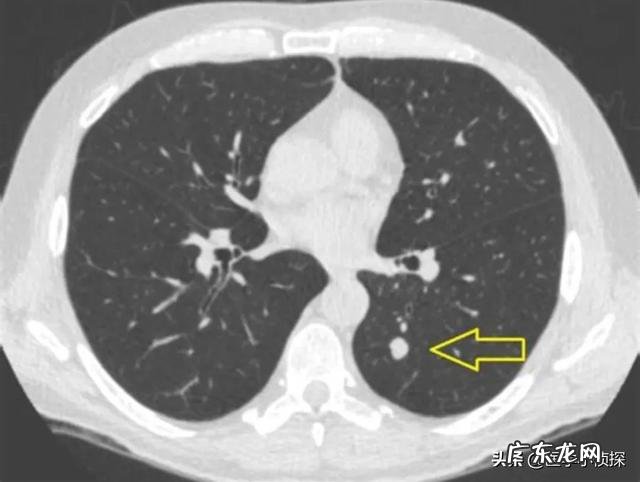

但注意 , 不是所有的伤疤 , 我们医生都把它叫做肺结节 , 而只有“伤疤”直径≤2cm的 , 我们就称为肺结节 , 并且发现我们肺部有结节 , 并不代表我们得了一种什么病 , 它只是如下图所示 , 我们影像科医生拍片 , 在我们肺部发现的一种影像学表现 。

文章插图